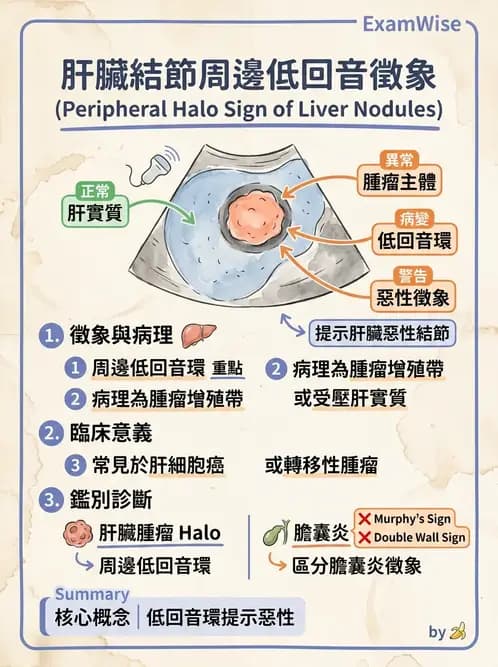

本題考查肝臟超音波(hepatic ultrasound)中肝內結節(intrahepatic nodule)的特殊影像徵象識別,特別是**周邊低回音徵象(peripheral halo sign)**的定義、超音波表現與臨床意義。

本張肝臟超音波影像顯示肝實質內有一圓形/橢圓形結節,其特徵如下:

- 結節整體回音不均勻,內部混合高低回音

- 結節周邊有一圈清晰的低回音暈環,與周圍正常肝實質形成明顯對比

- 影像上有測量游標(十字標記),標示結節的邊界與大小

- 此周邊低回音環即為**peripheral halo sign(周邊低回音徵象)**的典型表現

Peripheral halo sign 的病理基礎為:結節周邊有一圈增殖性腫瘤細胞帶,或受壓迫的正常肝實質,超音波下呈現低回音環狀構造。此徵象在肝臟惡性結節(如肝細胞癌或轉移性腫瘤)中常見。